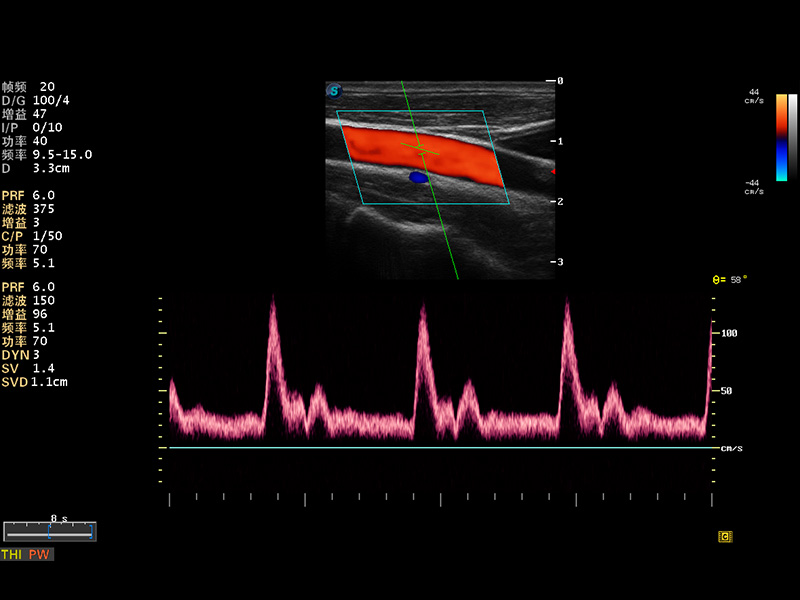

S8 EXP便攜式彩色多普勒超聲診斷儀是開立醫(yī)療研發(fā)的高端全身應(yīng)用型便攜彩超。高通道的VIS平臺(tái)融合可視化(Visual)、智能化(Intelligent)和人性化(Smart)的特點(diǎn),配以開立醫(yī)療自主研發(fā)生產(chǎn)的探頭大家族,使您能夠快速、準(zhǔn)確的獲得病人信息,提高工作效率的同時(shí)減輕疲勞。

成像技術(shù)

多波束形成器

μ-Scan微米成像

諧波成像

實(shí)時(shí)寬景成像

空間復(fù)合成像

3D/4D成像